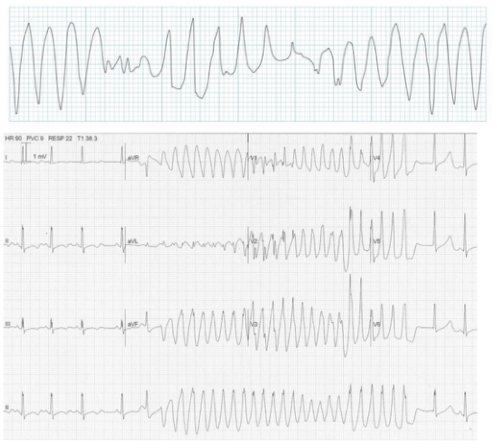

Polymorphic ventricular tachycardia with prolonged QT interval (Torsades de pointes)

Continuously changing amplitude

Rapid, irregular QRS complexes twisting around baseline

Associated with prolonged QT syndromes, electrolyte imbalance (hypomagnesaemia/hypokalaemia).

Often transient and intermittent